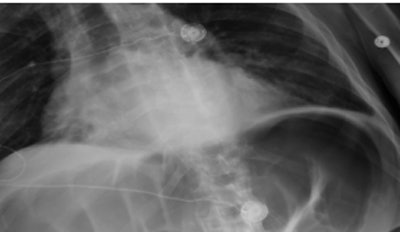

For the current study, the idea was to add a photograph that was inseparable from the patient's medical image, and the researchers also wanted to determine if the photographs were acceptable to the various providers involved in the patient care process. Technology developed at Emory embeds the photograph directly into the DICOM images using a camera installed on the x-ray system.

"When the x-ray tech triggers the machine, we get an x-ray from the patient and the camera gets a photo of the patient that includes the cassette ID plus the time stamp of the time the image was obtained," Sadigh. "All three -- the photo, the ID, and the time stamp -- go to a server and the server makes a DICOM image out of it."